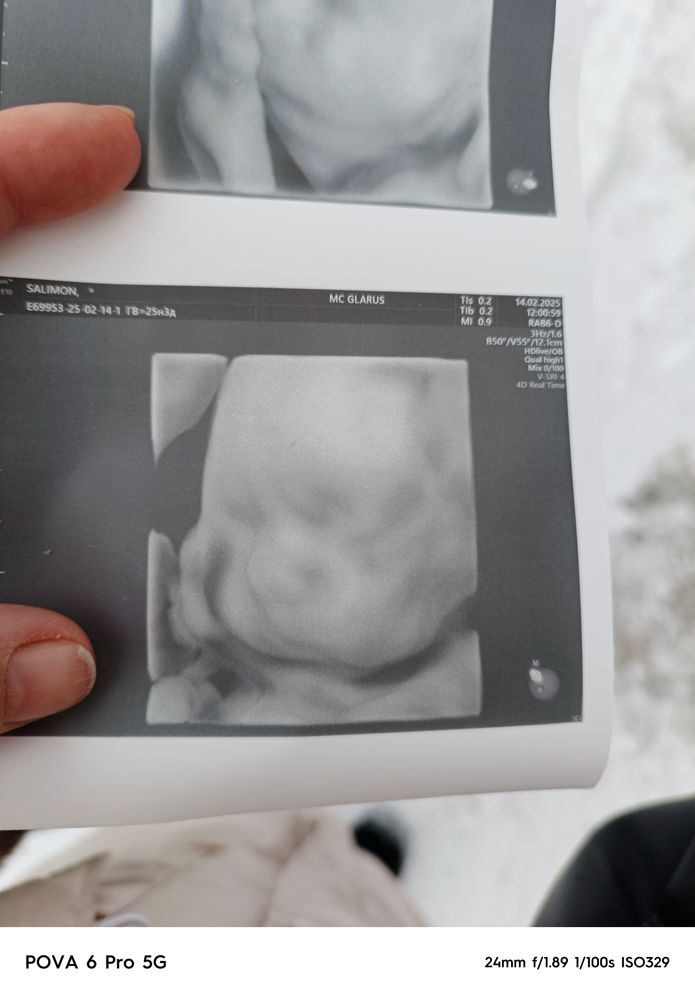

25 недель 3 дня

Сходили на узи, по ним все хорошо. Самый стеснительный парень, на узи пролежала 50 минут 😳 идем в срок. Шейка 37, вес бурундучка 930гр.